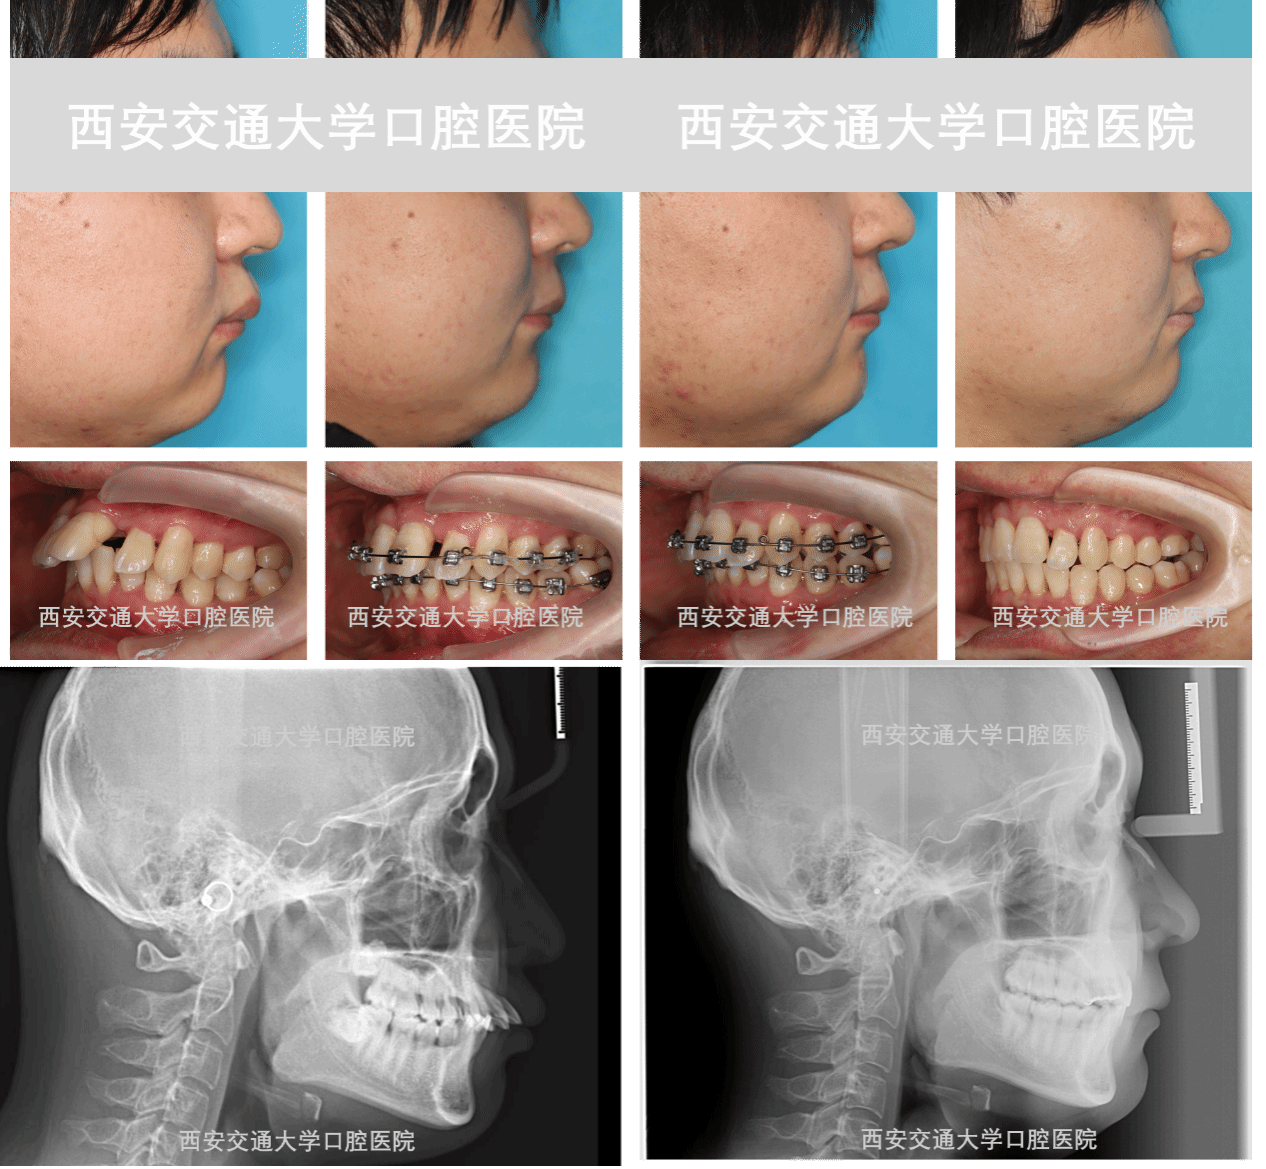

“没想到不仅没拔牙,还能恢复得这么好,解决了困扰我多年的问题,真的特别感谢王主任、陈主任和整个医疗团队!” 近日,在我院复杂牙颌颜面发育管理专科诊室,患者李先生顺利拆除佩戴三年的正畸矫治器,看着镜中排列整齐、咬合正常的牙齿,难掩激动与欣慰。这背后,是医院多学科团队三年来的精准诊疗与人文守护,更是“以患者为中心”医疗理念的生动实践。时间回溯至2022年,25岁的李先生发现上前牙间隙逐渐增大,影响美观与咀嚼功能,...